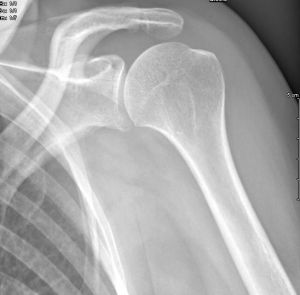

Les radiographies sont fréquemment requises entre autres, pour la recherche d'une fracture dans le cadre d'un traumatisme, les bilans d'arthrose, les bilans statiques, l'étude des poumons au cours d'une radiographie thoracique ...